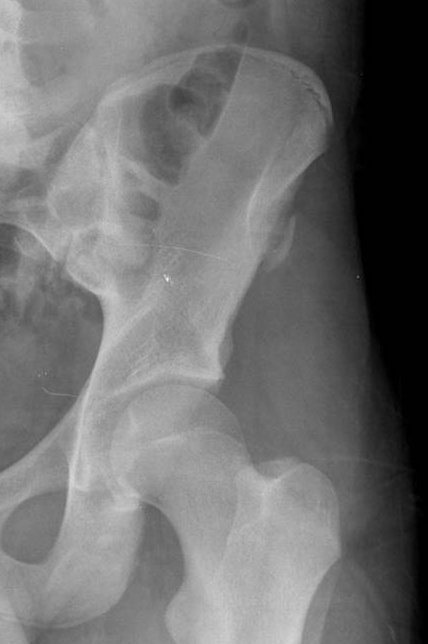

Any of the major muscle attaching to the pelvis or proximal femur may pull off at their attachment. This is classically a sporting injury, resulting from those resulting from extreme, unbalanced, often eccentric muscular contractions.

Once healing starts these lesions may mimic the appearance of an osteosarcoma, unfortunately so may the histology.